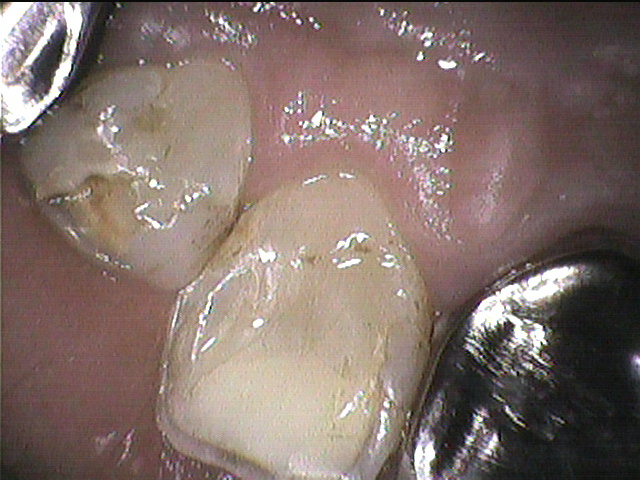

◎クリーニング前のお写真